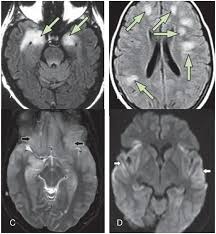

Diffusion Imaging In Brain Infections Radiology Key

Diffusion Imaging In Brain Infections Radiology Key from radiologykey.com

Two subtypes are recognized which differ in demographics, virus, and pattern of involvement. Become a gold supporter and see no ads. Bilateral temporal lobe t2 hyperintensity refers to hyperintense signal involving the temporal lobes on t2 weighted and flair imaging. Hypertrophic pachymeningitis is a condition where there is localized inflammatory thickening of the dura. Limbic encephalitis, mca ischaemia, tumours, effects of seizures) hyperintense t2 signal in the medial temporal lobes, inferior frontal lobes and insula basal ganglia are usually spared Reference osborn a, et al. Given the history of fever and seizures coupled with the mri findings of bilateral mesial temporal lobe changes, herpes encephalitis requires clinical consideration. The changes spare the basal ganglia, a feature which is helpful in distinguishing an mca infarct with hemorrhagic transformation from herpes simplex encephalitis, the diagnosis in this case. Mri demonstrates extensive edema in the right temporal lobe with areas of intrinsic high t1 signal, in keeping with hemorrhage. It is estimated to occur in ~2% of pati. The differential diagnoses include limbic encephalitis (paraneoplastic), gliomatosis cerebri, and status epilepticus. It is reasonable to obtain an mri when patients are asymptomatic to ensure that no other abnormality is present which may be causing a recurrent chemical meningitis (e.g. Axial t2 prominent swelling, increase t2 signal involving the left temporal lobe and insular cortex.

Axial t2 prominent swelling, increase t2 signal involving the left temporal lobe and insular cortex. Two subtypes are recognised which differ in demographics, virus, and pattern of involvement. Multilocularis.the larval stage is the cause of hydatid disease in humans 1. Cerebral malaria is a rare intracranial complication of a malarial infection. The changes spare the basal ganglia, a feature which is helpful in distinguishing an mca infarct with hemorrhagic transformation from herpes simplex encephalitis, the diagnosis in this case.